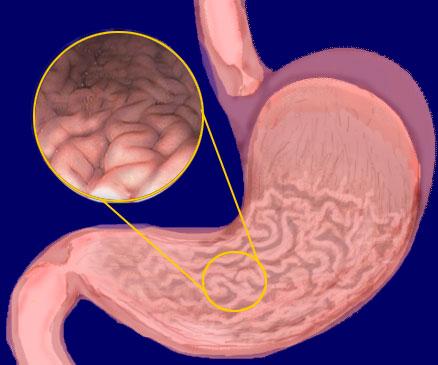

Body (of stomach)

Cardia (of stomach)

Fundus (of stomach)

Gastroesophageal sphincter

Pyloric Sphincter

Pylorus (of stomach)

Rugae (of stomach)

Stomach